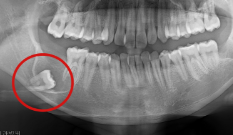

Case 07. 매복된 치아 & 쓰러진 어금니

영구치가 잘못된 방향으로 나거나 제때 올라오지 못하면 턱뼈 속에 갇히는 ‘매복 치아’가 생기며, 교정 치료로 올바른 방향으로 유도·견인해 정상교합 관계를 회복합니다.

어금니가 빠진 뒤 오랫동안 방치하면 인접 치아가 쓰러지고 맞물리던 치아가 내려오는데, 이 경우 쓰러진 어금니를 세우고 위치를 바로잡는 교정 치료로 씹는 힘과 치열의 균형을 되찾을 수 있습니다.

교정 치료 Before & After

• 매복된 치아

Before

After

• 쓰러진 어금니